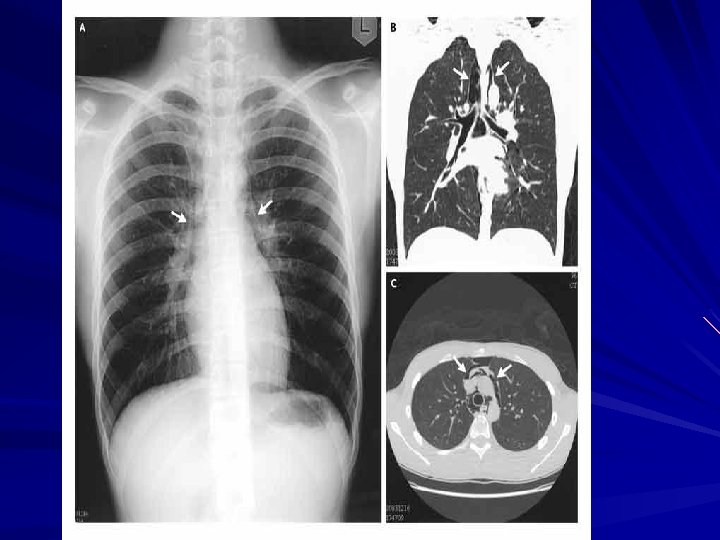

Diagnosis CXR may show air-fluid level Barium study quite dilated, and an airfluid level may be secondary to retained secretions. The classic finding is a gradual tapering at the end of the esophagus, similar to a bird's beak Upper endoscopy is the next diagnostic test in a patient with dysphagia or suspected achalasia

Symptoms and Diagnosis of an esophageal perforation may be made radiographically A chest roentgenogram may demonstrate a hydropneumothorax A contrast esophagram is done using barium for a suspected thoracic perforation and Gastrografin for an abdominal perforation.

Symptoms and Diagnosis Most perforations are found above the GEJ on the left lateral wall of the esophagus which results in a 10% false -negative rate in the contrast esophagram if the patient is not placed in the lateral decubitus position Chest CT shows mediastinal air and fluid at the site of perforation